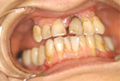

Q 実際にT-typeを臨床に用いられた症例における感想をお聞かせください。

また抜歯即時症例にも数例適応しましたが、すべて良好な経過をたどっています。 通常の症例にもT-typeは対応することが可能だと考えますが、フィクスチャー12?のものがあればさらに適応症例が広がると考えています。